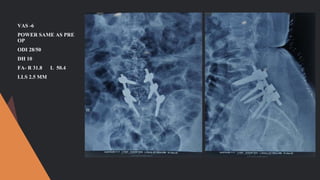

POST OP

POWER 5/5

ODI - 16/50

VAS – 3

DH-8 MM

FA – R 40 L 37